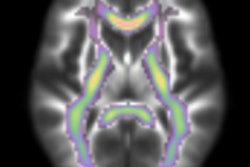

The researchers, led by Dr. David Perez from MGH's departments of neurology and psychiatry, compared whole-brain structural MRI scans of 26 FND patients with those of 27 healthy control subjects. Their goal was to find associations between the size of network structures and the participants' physical and mental health and symptoms of anxiety and depression.

While the researchers found no whole-brain structural differences between the FND patients and healthy controls, they did observe a link between decreased volume in the left anterior insula and higher levels of physical impairment. Meanwhile, patients with the greatest mental health impairments and highest anxiety levels had increased volume within the amygdala.